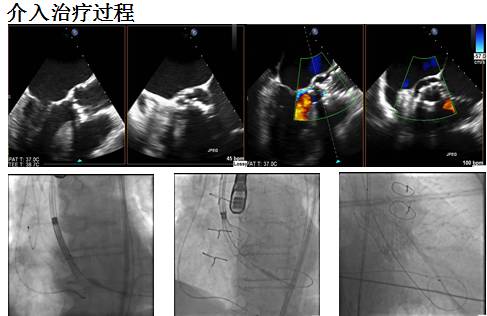

Case 1

◆男性,87岁

◆主诉:进行性劳力性呼吸困难12月,上斜坡时明显,无胸痛或晕厥

既往史:1992年冠脉搭桥,永久性房颤,高血压3级,左肾动脉70%狭窄

◆辅助检查:

Hb: 90, Cr 65 (CC: 90), BNP: 202

经胸心脏超声:三叶式主动脉瓣,瓣叶明显增厚、钙化,开放受限,PG max62/mean37mmHg, AVA 0.54 cm2, EF 47%, mild AR; Mild-moderate MR, Moderate TR

冠脉造影: RCA & LAD桥血管通畅